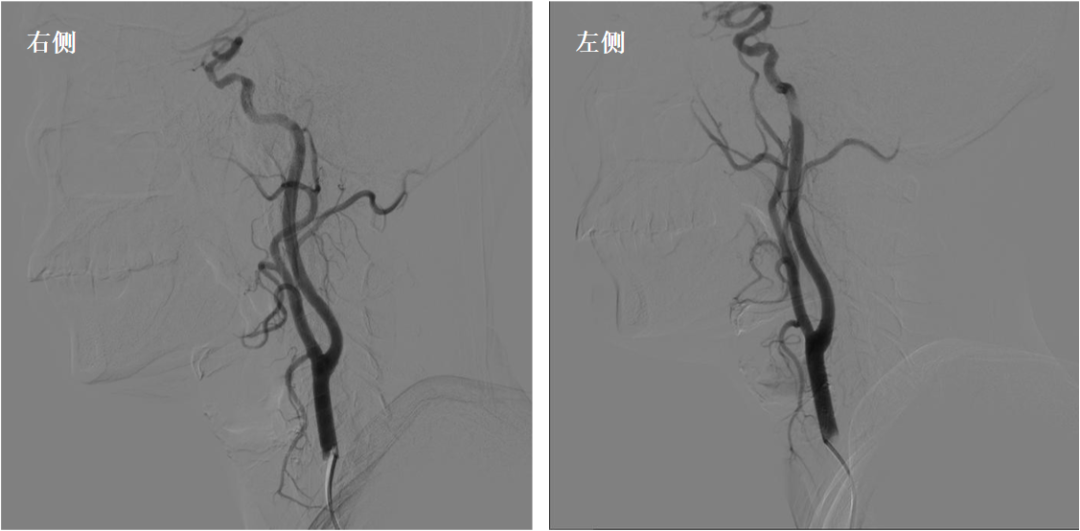

调整SIM2导管头端位置,将造影导丝放入降主动脉,SIM2管随造影导丝进入降主动脉;撤回造影导丝,顺时针或逆时针轻轻扭动SIM2导管,让其成袢;慢慢回拉成袢的SIM2导管,让其头端跳入左锁骨下动脉口,造影剂冒烟证实后,适当调整导管头端位置和张力后,行左侧锁骨下动脉造影;若有需要,可沿导管置入泥鳅导丝超选进入左侧椎动脉,行左椎动脉超选造影;旋转并内送SIM2导管让其再次成袢,缓慢回拉并适当旋转导管,让导管头端自然跳入左侧颈总动脉,必要时可适当旋转导管,帮助其寻找到左侧颈总动脉;旋转导管解袢,行左侧颈总动脉造影,或用泥鳅导丝协助超选进入左侧颈内动脉,行左侧颈内动脉超选造影;旋转并内送SIM2导管让其再次成袢,缓慢回拉并适当旋转导管,让导管头端自然跳入无名动脉;导管进入无名动脉后,边回拉边冒烟,让导管头端对准右侧颈总动脉并顺利进入,解开导管袢,必要时用泥鳅导丝助其超选进入右侧颈内动脉,完成右侧颈内动脉造影;回拉导管至右侧锁骨下动脉,冒烟证实在右侧椎动脉口附近时,行右侧锁骨下动脉造影;路途下,用泥鳅导丝把SIM2管带入右侧椎动脉,行右侧椎动脉超选造影。

颈总动脉造影

右侧颈内动脉超选造影

左侧颈内动脉超选造影